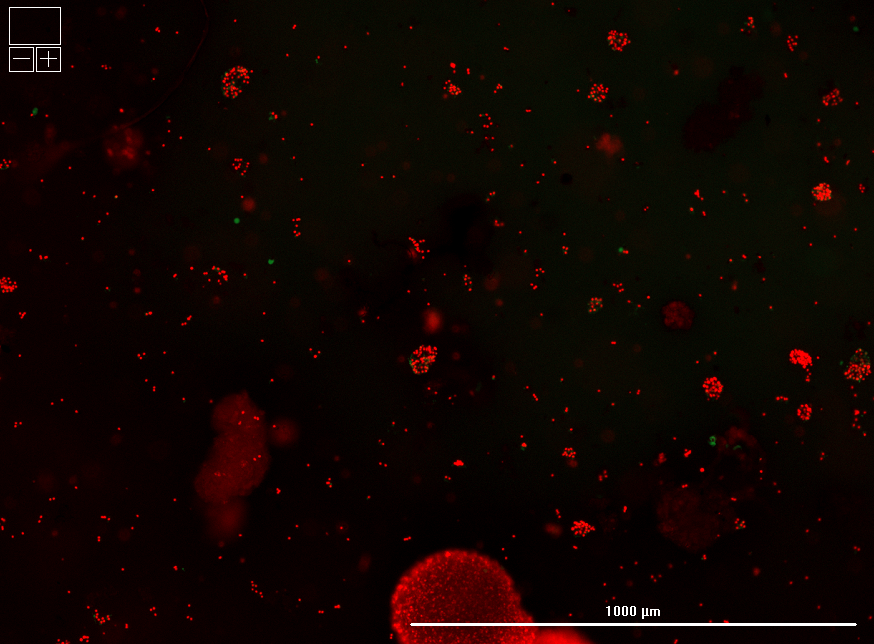

Encapsulated islets retained high viability and cellular integrity compared to standard (unencapsulated) cryopreservation, as confirmed by live/dead imaging.

Hydrogel polymer formulation #2 yielded superior survival and uniform morphology relative to formulation #1, highlighting tunability of the LiberaCell™ system.